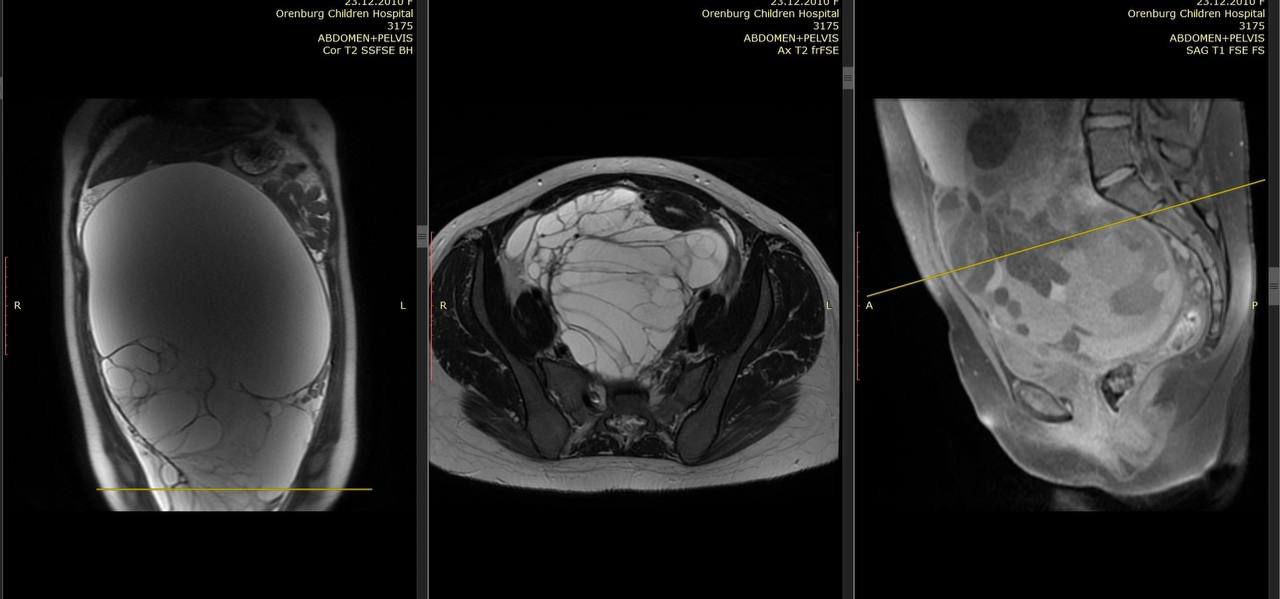

В Оренбурге медики провели уникальную операцию, в результате которой была удалена гигантская опухоль весом 8 килограммов у 13-летней девочки. Это важное событие стало настоящим прорывом в области детской хирургии и доказательством высокого уровня квалификации врачей.

Операция проводилась в условиях высоких рисков, но благодаря слаженной работе команды хирургов, анестезиологов и медицинского персонала, удалось добиться положительного результата. Перед операцией девочка прошла все необходимые обследования, которые подтвердили наличие опухоли и ее размеры.

По словам врачей, такая опухоль является редким заболеванием в педиатрической практике, и ее удаление потребовало особой техники и опыта. Хирурги использовали современное оборудование и методы, что позволило минимизировать травмы и ускорить процесс восстановления пациентки.